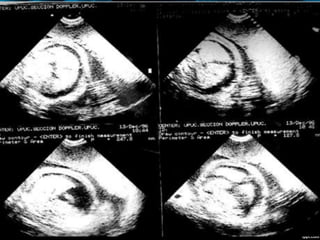

CASOS CLINICOS

INMUNOLÓGICO.

PACIENTE MULTÍPARA DE 26 AÑOS

DE EDAD, O RHO (-).

PAREJA B RHO (+)

CON EMBARAZO DE 28 SEMANAS.

TÍTULOS ANTIRH 1/1024,

ESPECTROFOTOMETRÍA DEL LÍQUIDO

AMNIÓTICO: ZONA DE ALTO RIESGO DE

QUEENAN, ZONA III DE LILEY.

CORDOCENTESIS: HB. FETAL 3 G. %.,

HTCO. FETAL 10%.

TIPIAJE FETAL B RHO(+).

SE REALIZA TRANSFUSIÓN

INTRAVASCULAR 40 CM3 DE

CONCENTRADO GLOBULAR O RH(-).

HALLAZGOS ECOGRÁFICOS: ASCITIS,

DERRAME PLEURAL, EDEMA SUBCUTÁNEO,

EDEMA PLACENTARIO.